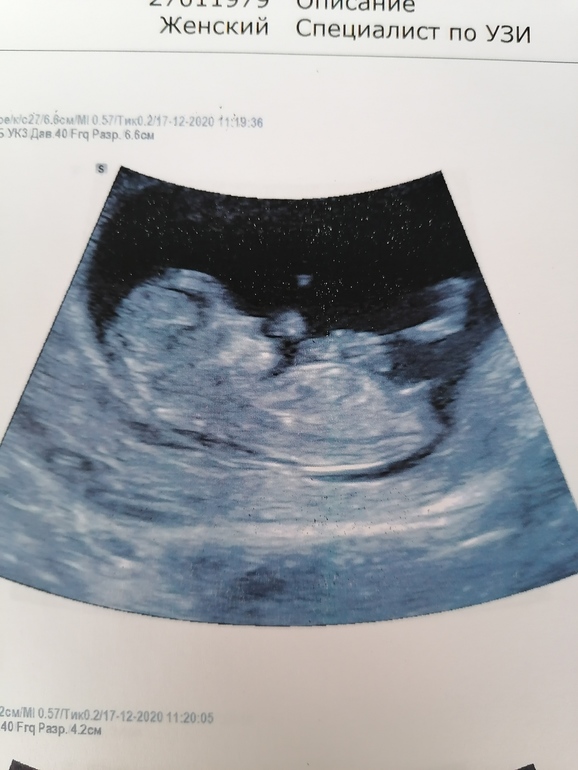

Перед узи он спросил о количестве беременностей и я сказала, что у нас 6 дочек, про НИПТ я не сказала. Все узи он коментировал и все показывал нам. И вот в самом конце рассказав, что все с малышом хорошо, он сказал, что это МАЛЬЧИК💙💙💙. Со мной реально случился приступ, я разве, что не кричала в голос, слезы текли градом, я вся покрылась мурашками и причитала " сыночек, родной мой как долго мы тебя ждали" 🥰🥰🥰. Показали нам пипрку 💙💙💙👶 нашего СЫНА. Как же долго я ждала этого, увидеть на узи пистолет, а не пирожок🥰🙏🙏🙏.